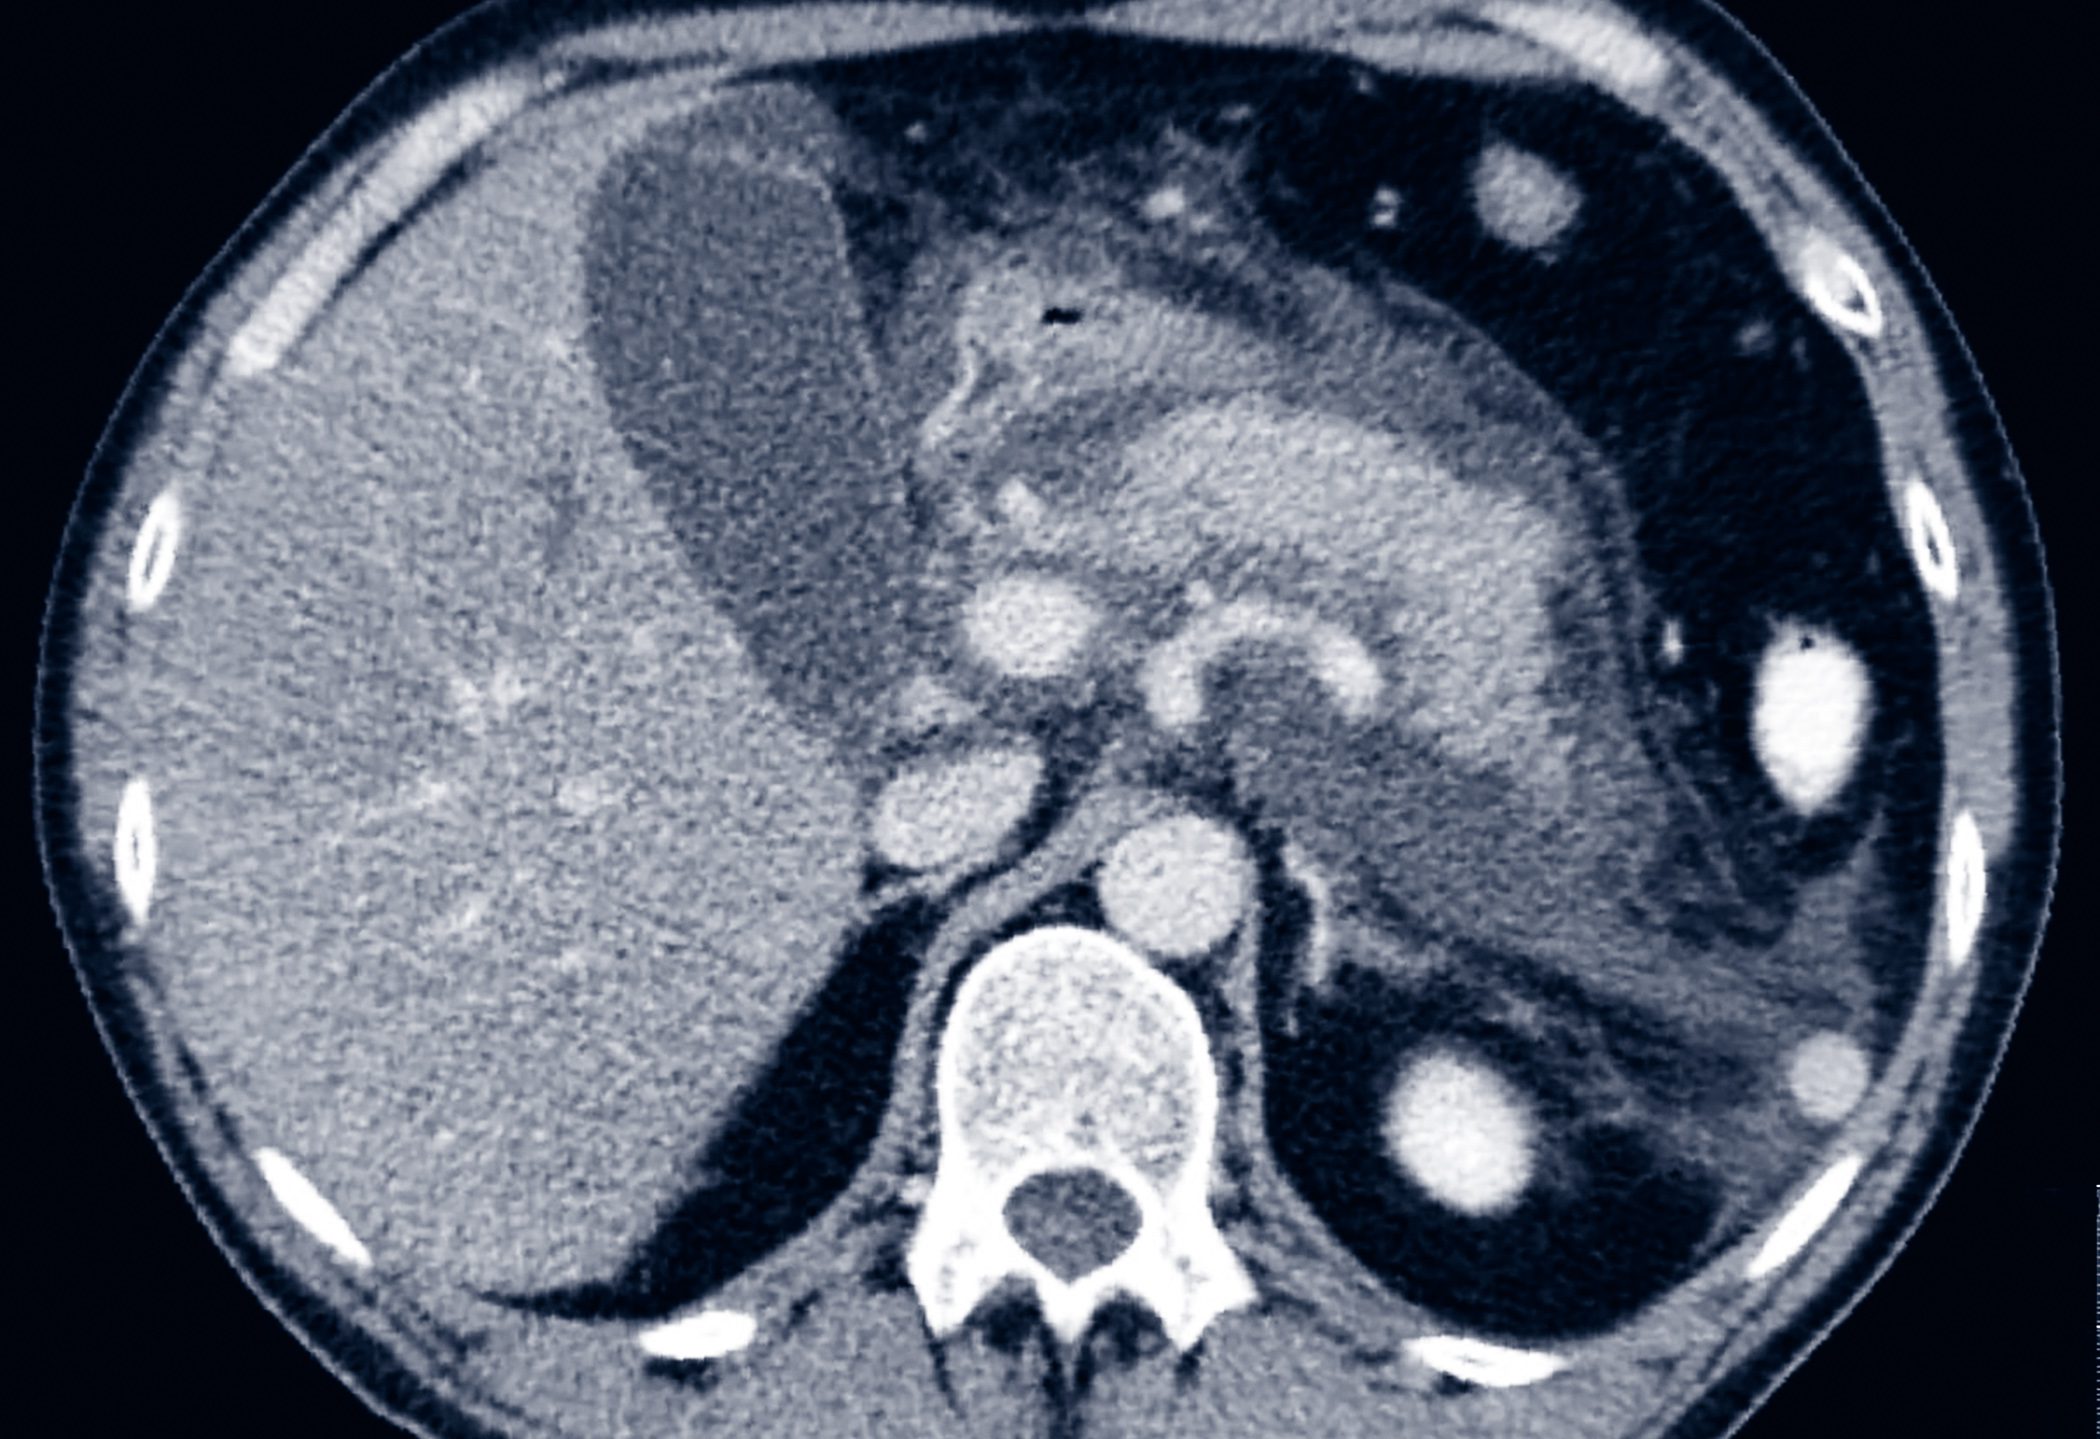

• Vom Symptom zur Diagnose

Komplizierte Nierenzysten

• Rx

• Cases

• Fortbildung

• Nephrologie

• Onkologie

• Radiologie

• Urologie

Weiterlesen